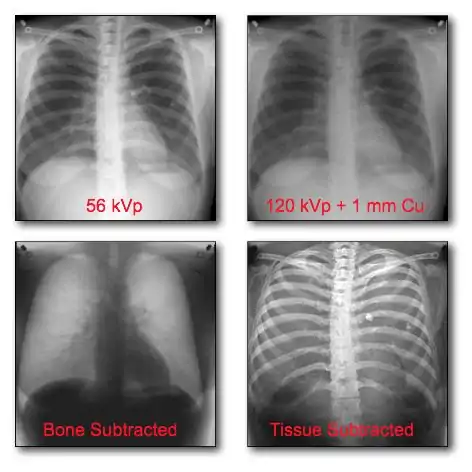

Dual-Energy Imaging

- CR and DR image receptors can generally be used for dual-energy radiography in either of two configurations:

- Dual exposures: where two separate exposures are used in applications where patient movement isn't an issue; and

- Single exposure: where two imaging plates separated by a filter are mounted in a dual-energy cassette to record the low energy image on the anterior plate and the high energy image on the other.